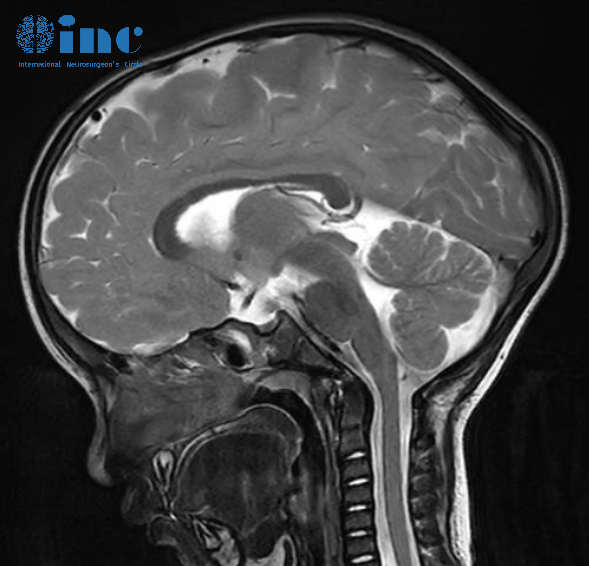

第一次检查,脊髓MRI显示脑膜覆盖多处结节性病变;颅脑MRI可见脑膜明显强化,尤其是脑干腹侧表面上的软脑膜。